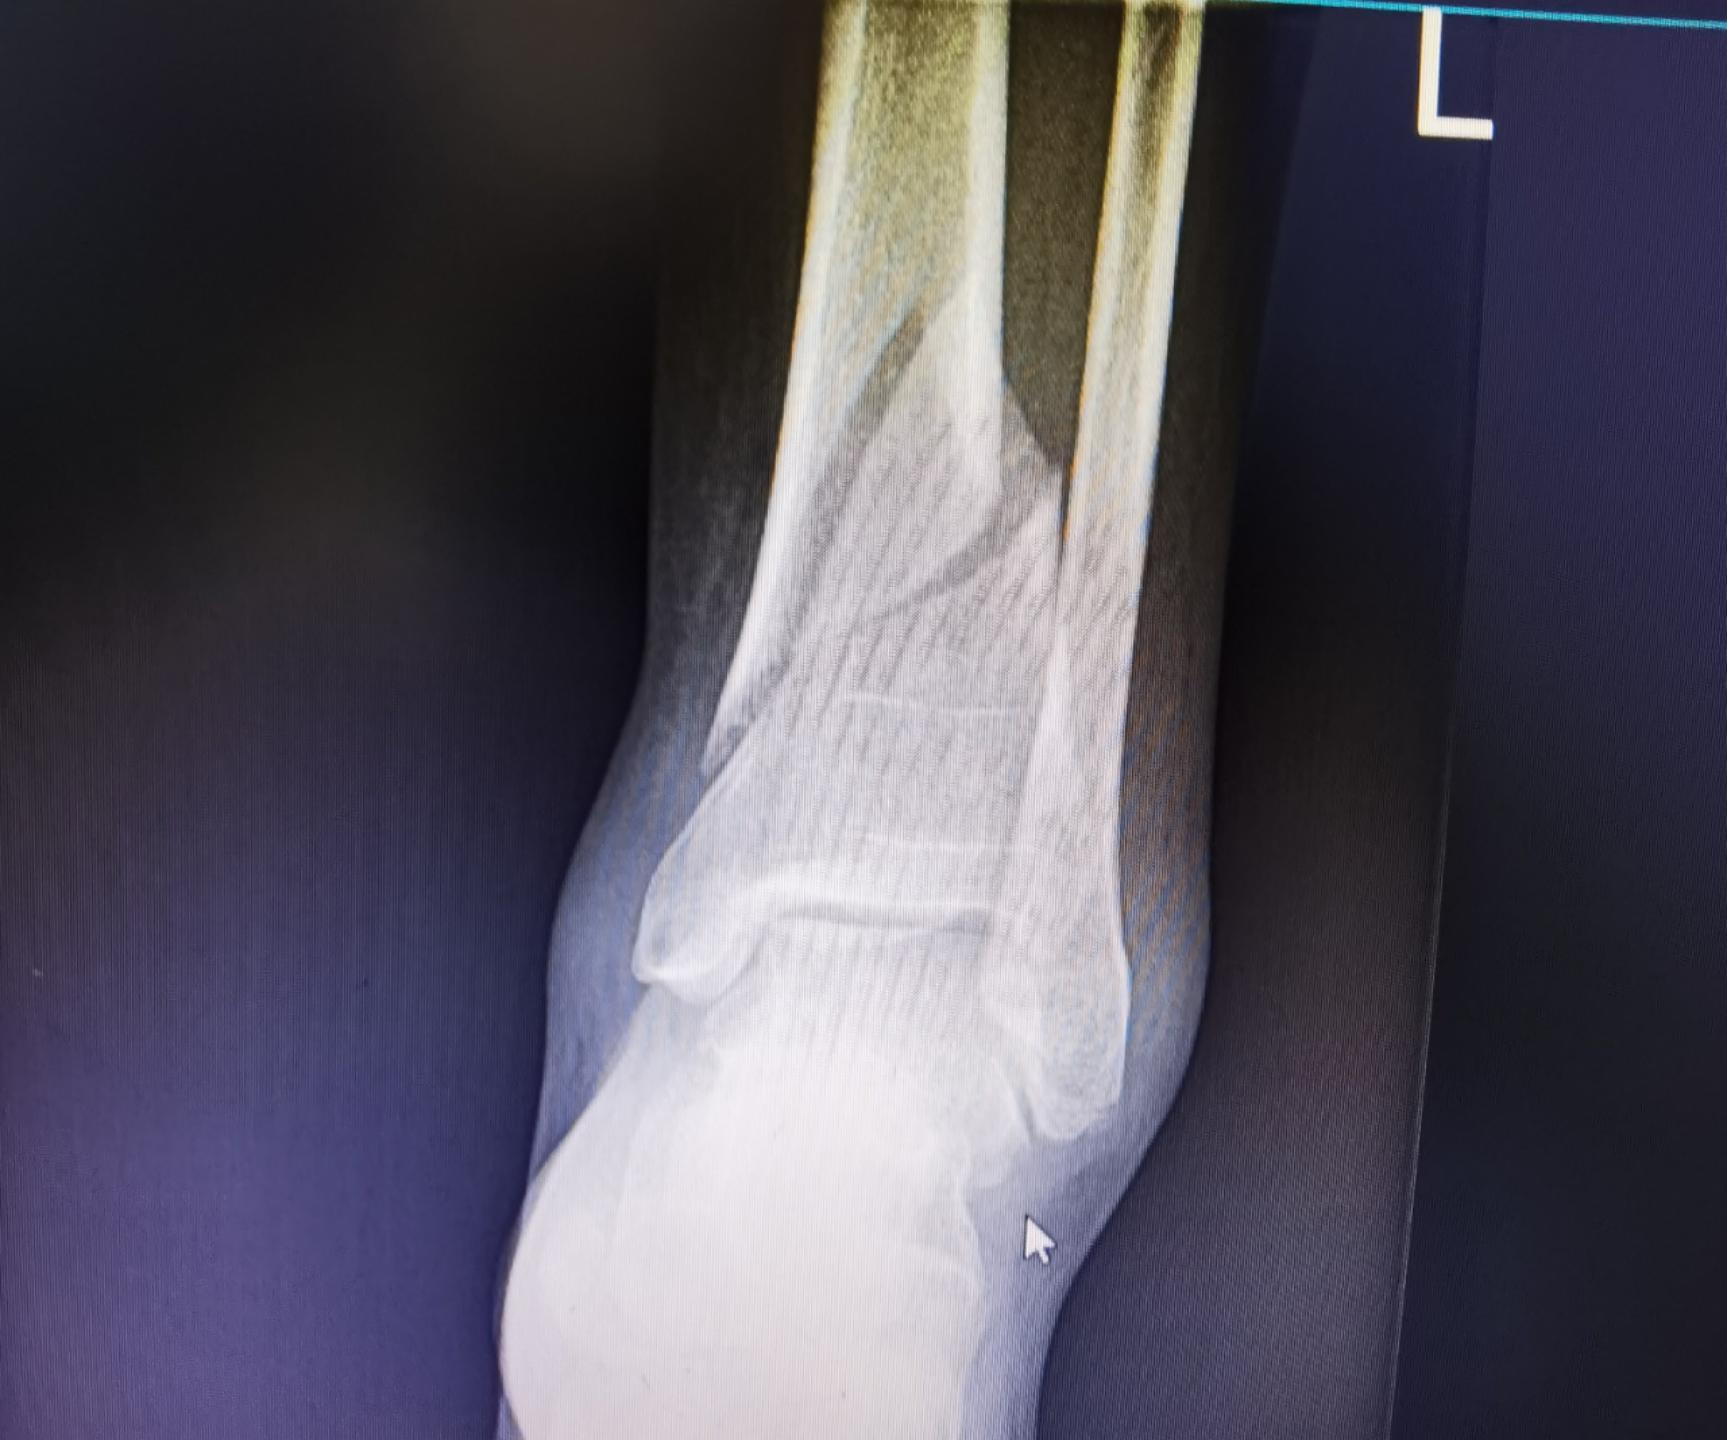

做完CT检查后,结果显示为:左侧胫骨远端骨折,左侧腓骨下段骨折,部分断端可见错位,局部软组织肿胀,需要即刻住院,并安排手术治疗。